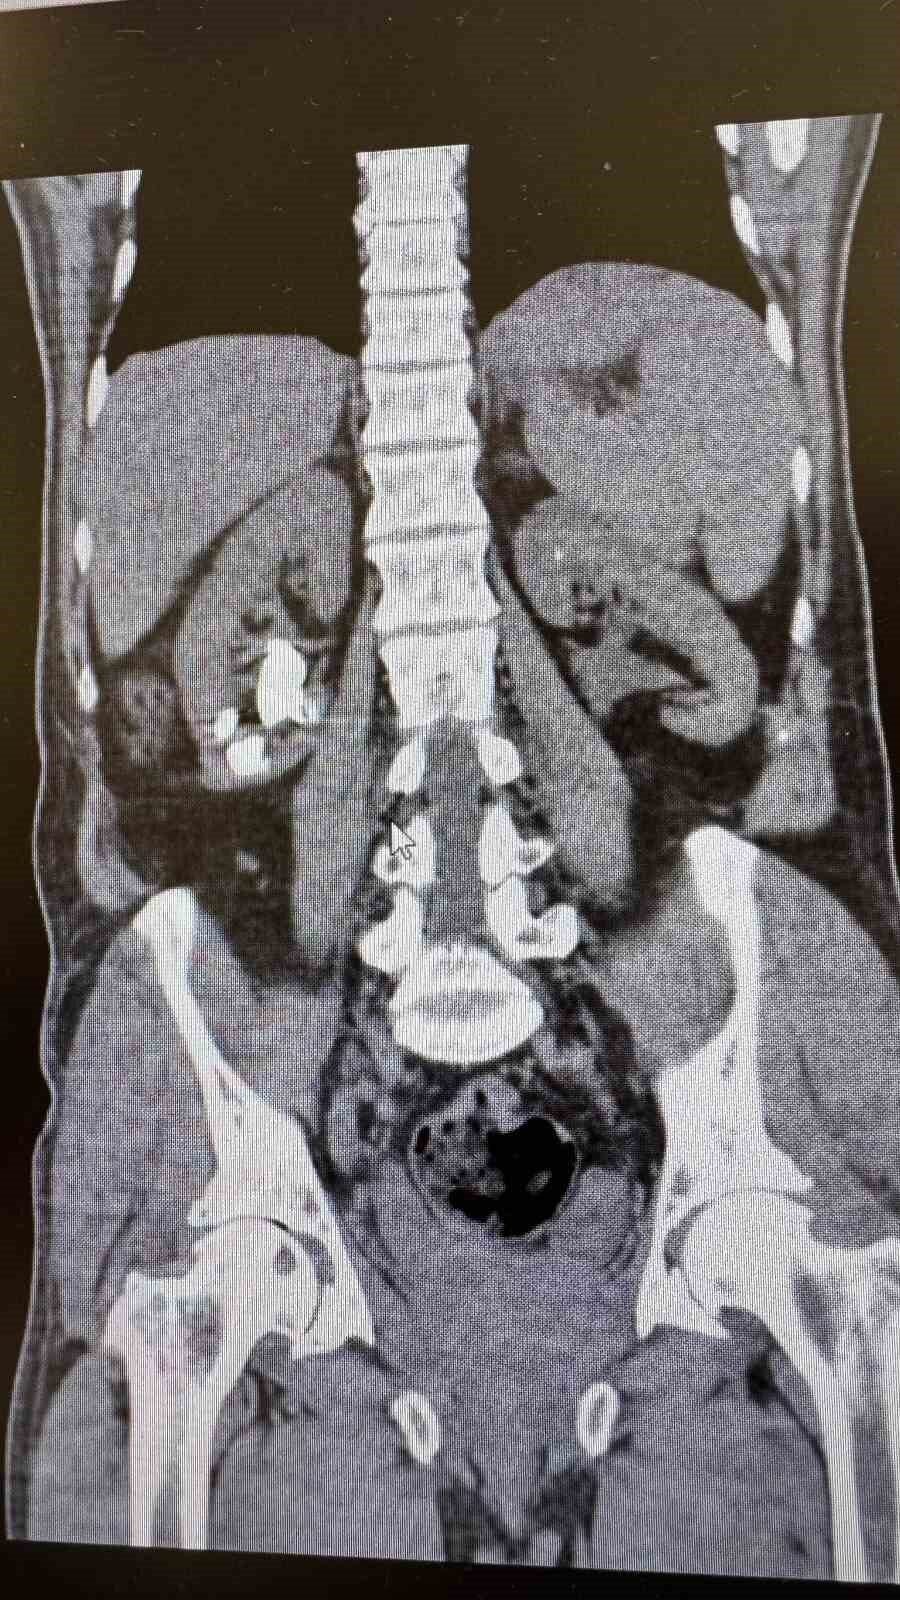

Antalya Gazipaşa Devlet Hastanesi’nde gerçekleştirilen iki başarılı operasyonla 62 yaşındaki hasta böbrek taşlarından tamamen kurtuldu.

Üroloji Uzmanı Op. Dr. İlker Fatih Şahiner ve ekibince kapalı yöntemle (PNL) yapılan ameliyatlarda hastanın her iki böbreğindeki tekrarlayan sistin taşları temizlendi. Hastanın daha önce 10’un üzerinde böbrek taşı ameliyatı geçirdiği öğrenildi. Mayıs ayında yapılan ilk operasyonla sol böbrekteki taşlar alınırken, geçtiğimiz salı günü gerçekleştirilen ikinci operasyonla sağ böbrekteki taşlar da temizlendi.

Operasyonları gerçekleştiren Üroloji Uzmanı Op. Dr. İlker Fatih Şahiner, “Hastamızın her iki böbreğinde de tekrarlayan sistin taşları mevcuttu. Mayıs ayında sol böbreğine PNL yaparak taşsızlık sağlamıştık. Dün de sağ böbreğine PNL ameliyatını yaparak taşsızlık sağladık. Hastamızın genel durumu iyi, tedavisi servisimizde devam ediyor” dedi.